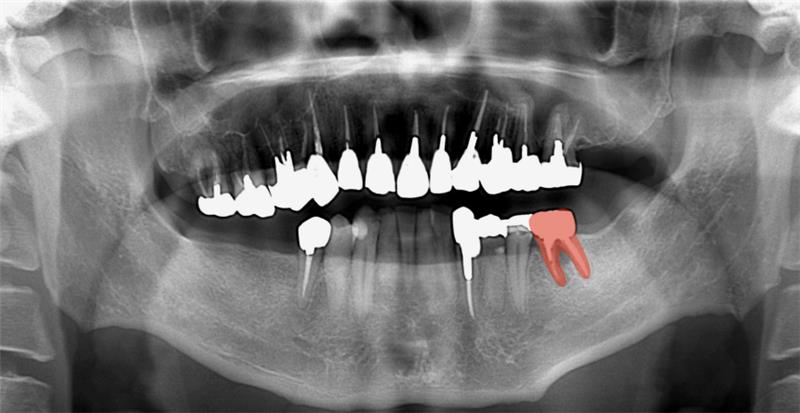

今回ご紹介する患者さんは40代の男性で、奥歯の欠損と歯並びの乱れによってかみ合わせが不安定な状態でした。奥歯がないことで、しっかり噛むことが難しく、全体のバランスも崩れていました。

※初診時の口腔内とレントゲンの写真

この場合、インプラントを先に行い、奥歯の噛み合わせを安定させてから矯正を行うことが重要です。一方で、こちらのケースでは理想モデルを組んだ結果、矯正で歯を動かす量が大きいことが判明しました。